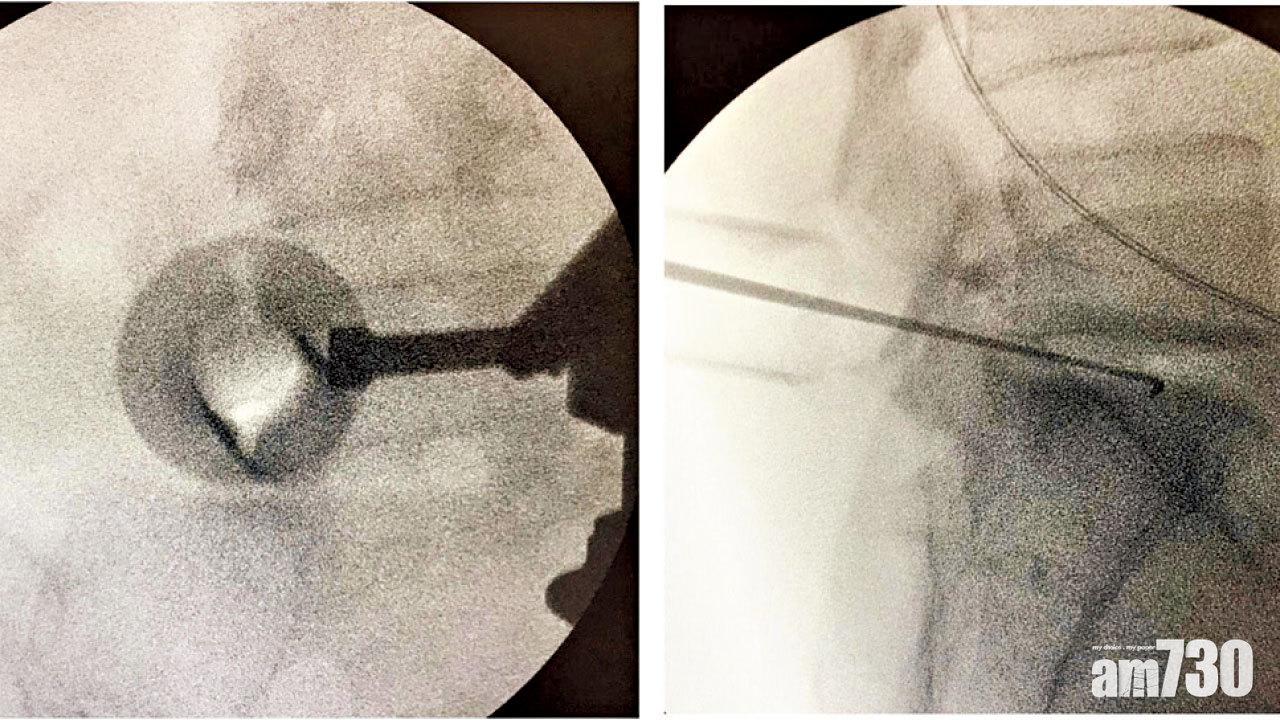

然而,X光會把三維骨骼投影在二維底片上,單從一個角度來看,便有可能導致「斷錯症」。故此,一張正位(Anteroposterior)加上一張側位(Lateral)X光片,便大致能夠讓骨科醫生,在腦海中重建骨骼的三維結構,以評估骨折移位和關節退化的程度。有時候更須在正側之外,加上斜位或指定角度的X光。而這種肉眼看不到的X光,更在手術過程中協助醫生,評估骨折復位和植入金屬位置是否良好;以及在脊椎手術期間,判定開刀位置正確無誤(見圖)。